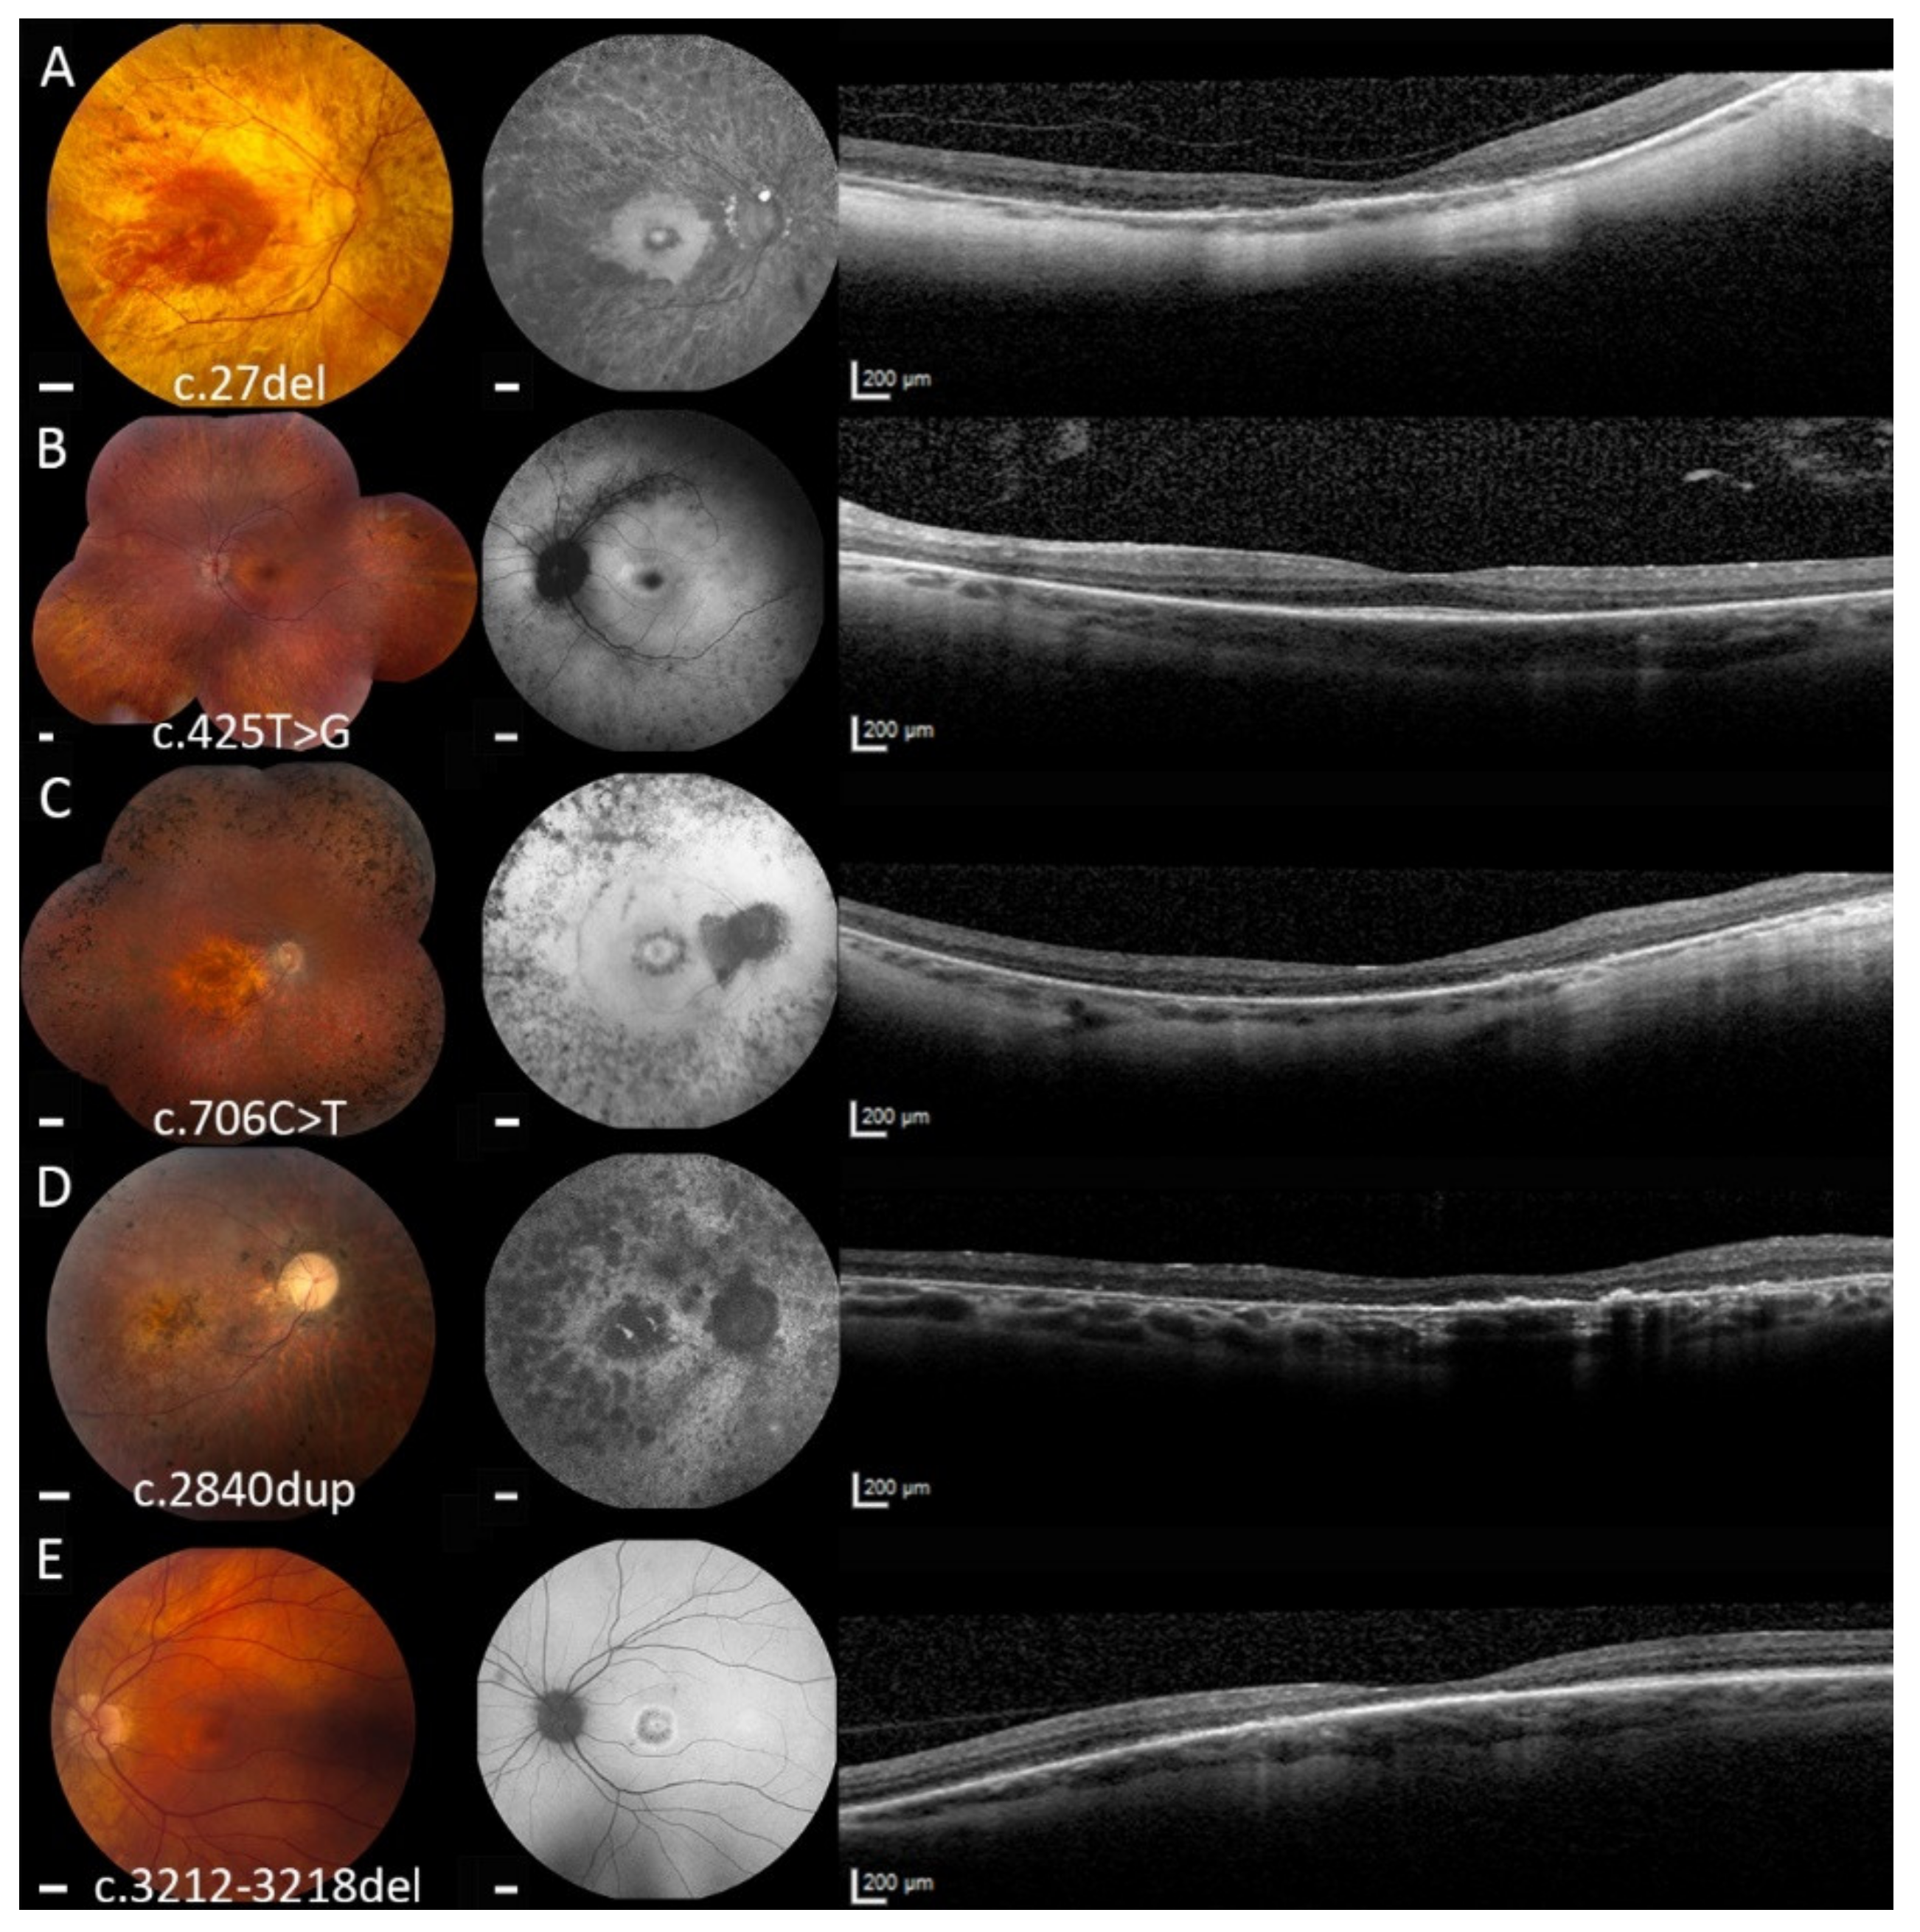

2.1. Clinical Examination